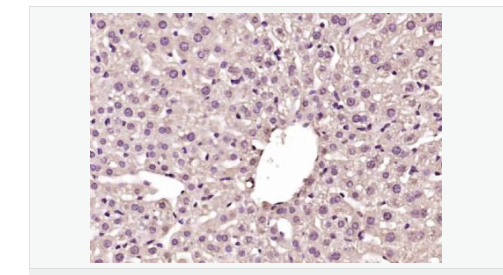

產品介紹GCKR is a subfamily member of the SIS (Sugar ISomerase) family of proteins. It is a regulatory protein that inhibits glucokinase in liver and pancreatic islet cells by binding non-covalently to form an inactive complex with the enzyme. This gene is considered a susceptibility gene candidate for a form of maturity-onset diabetes of the young.

Tissue Specificity:

Found in liver and pancreas. Not detected in muscle, brain, heart, thymus, intestine, uterus, adipose tissue, kidney, adrenal, lung or spleen.